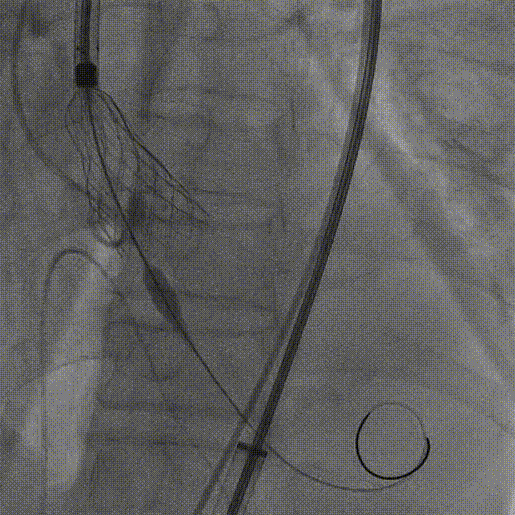

3.20mm球囊预扩,轻微腰征,冠脉显影良好,无造影剂渗漏

20mm球囊预扩

2.22mm球囊预扩,无明显腰征,冠脉显影良好,无造影剂渗漏。

22mm球囊预扩